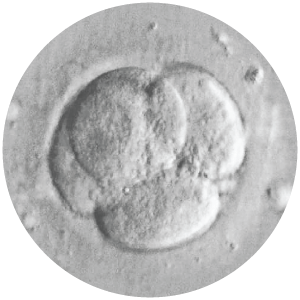

Biopsy Workshop

Our biopsy workshop offers hands-on practice with the Lykos DTS laser. Whether you’re new to embryo biopsy or an experienced practitioner looking to explore new equipment and the latest techniques, this workshop will be customized to your needs and showcase state-of-the-art technology.